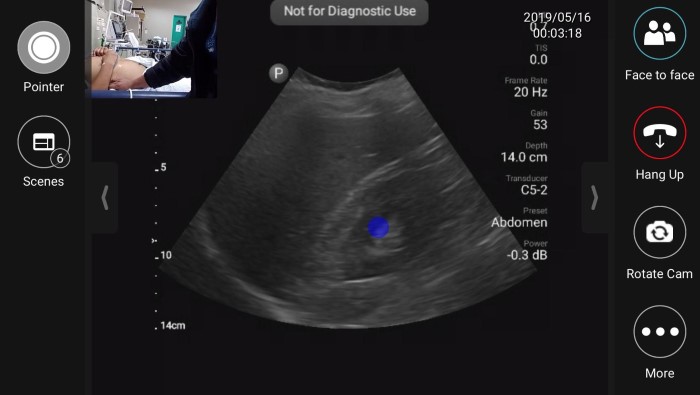

EUS_10-2024-Article1-1.jpgFigure 1. Tele-ultrasound platform as visualized by remote user providing diagnostic/procedural assistance

During the initial months of the fellowship, onsite support during the fellow’s scanning shifts was provided by volunteer visiting instructors from the US. Following this initial period, visiting instructors were not always present in Lima, however fellows could utilize the built-in tele-ultrasound software on the handheld ultrasound device to contact a pool of on-call physicians during their required ultrasound scanning shifts. The inaugural year of the fellowship we primarily relied on tele-ultrasound to provide live support during the fellow’s self-directed scanning shifts whenever questions arose.

In 2020, year three of the fellowship, we were forced to adapt to strict travel restrictions enforced due to the COVID-19 pandemic. We suddenly were forced to rely primarily on tele-ultrasound to provide ongoing teaching and support. We shifted from utilizing tele-ultrasound on an as needed basis to scheduling tele-ultrasound scanning shifts accompanied by a senior ultrasound fellowship trained instructor located either in the US or Peru. An added benefit of having graduated five classes of fellows to date is that we can now rely on former fellowship graduates to host tele-ultrasound sessions with the new class of fellows.